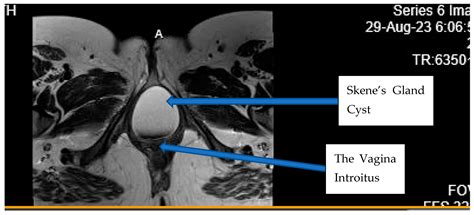

The Skene glands, also known as the paraurethral glands, are located on the anterior wall of the vagina, specifically around the lower end of the urethra. They are considered the female equivalent of the prostate gland in males. These glands are responsible for secreting a lubricating fluid that helps keep the urethral opening moist. When the ducts of these glands become obstructed or infected, the fluid cannot drain properly, leading to the formation of a Skene Gland Cyst.

While many people may go their entire lives without realizing they have these glands, issues arise when the ductal opening is blocked. This blockage causes the fluid to accumulate, eventually forming a visible or palpable lump. These cysts can vary in size, ranging from a small pea to a larger, more painful growth.